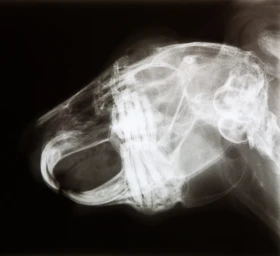

Stomatologie drobných savců je rychle se rozvíjejícím odvětvím veterinární medicíny. V posledních letech stoupá obliba chovu drobných savců jako domác...